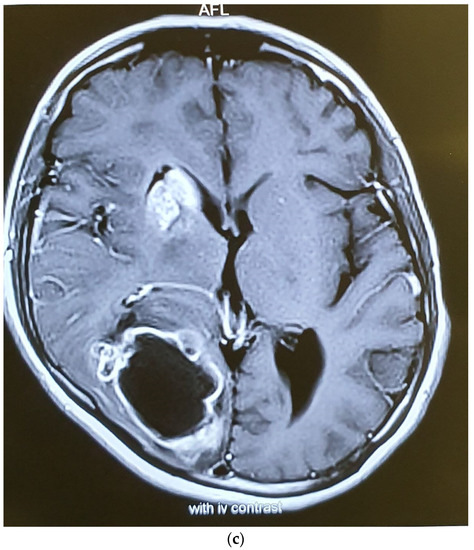

| The current case | 29, female | C2 | CD45, CD43, CD68, S100 | Surgery and radiotherapy | Brain metastasis after 9 months |